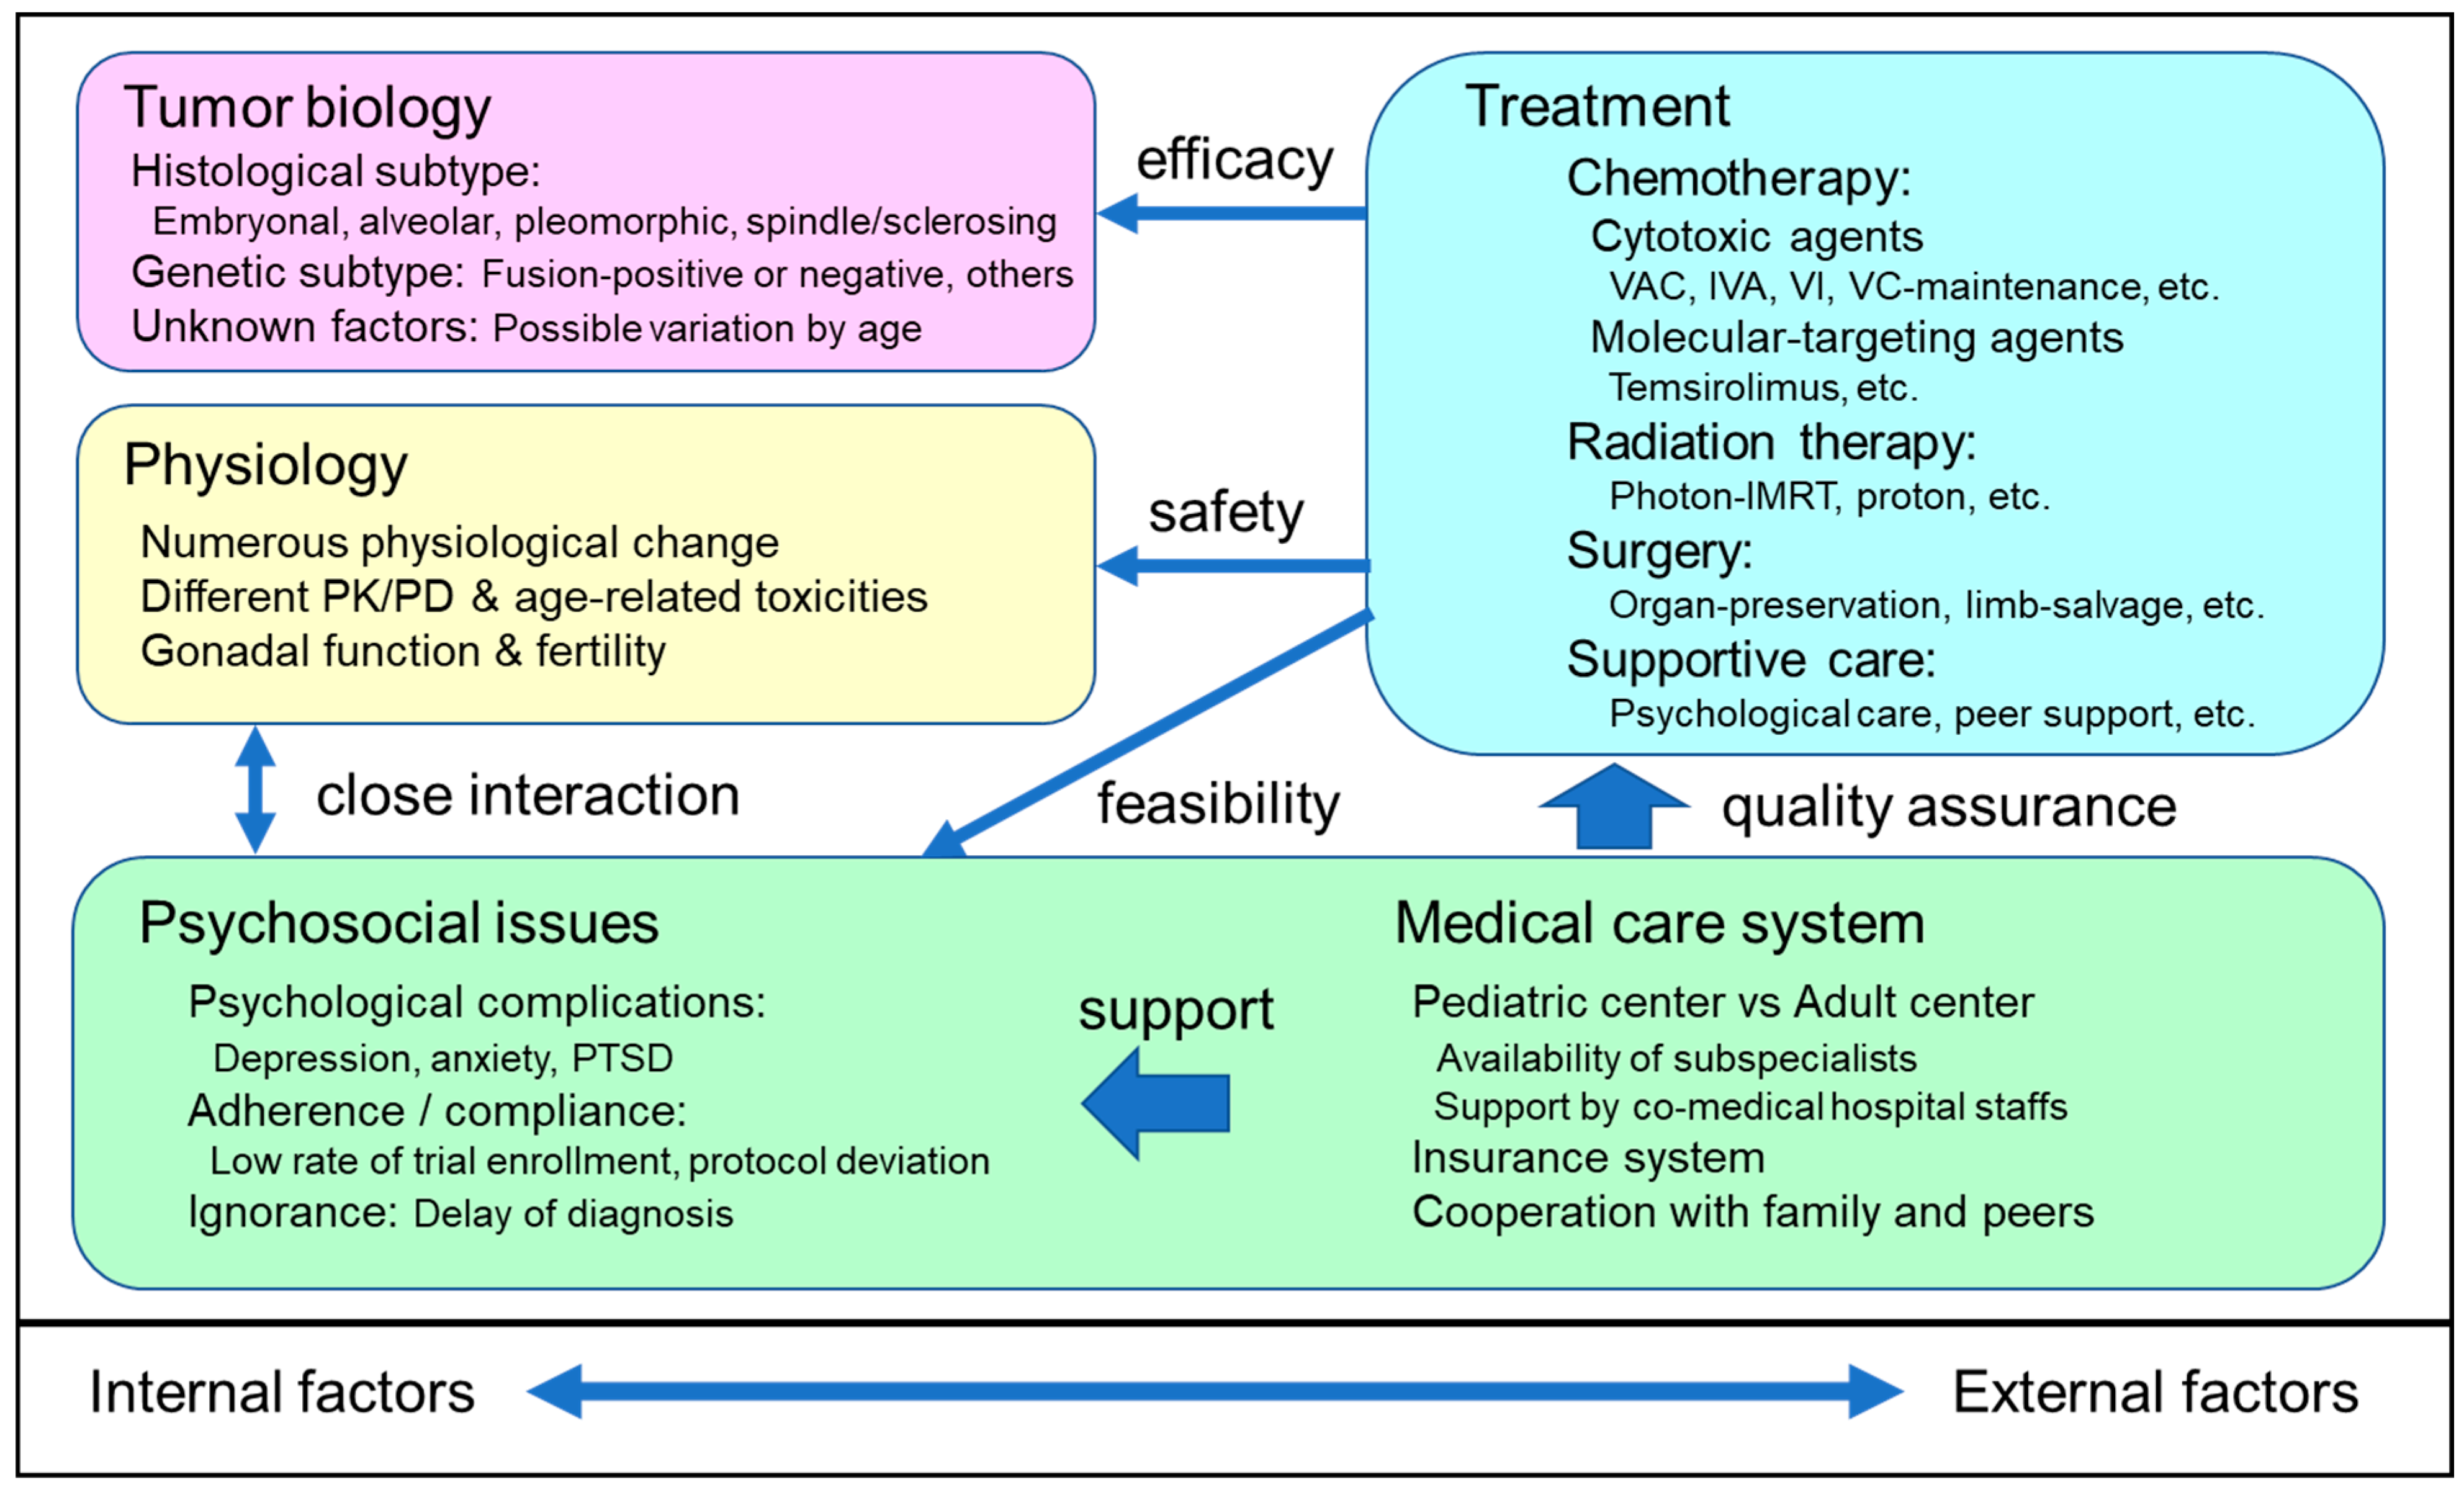

Cancers | Free Full-Text | Optimizing Rhabdomyosarcoma Treatment In

www.mdpi.com

www.mdpi.com